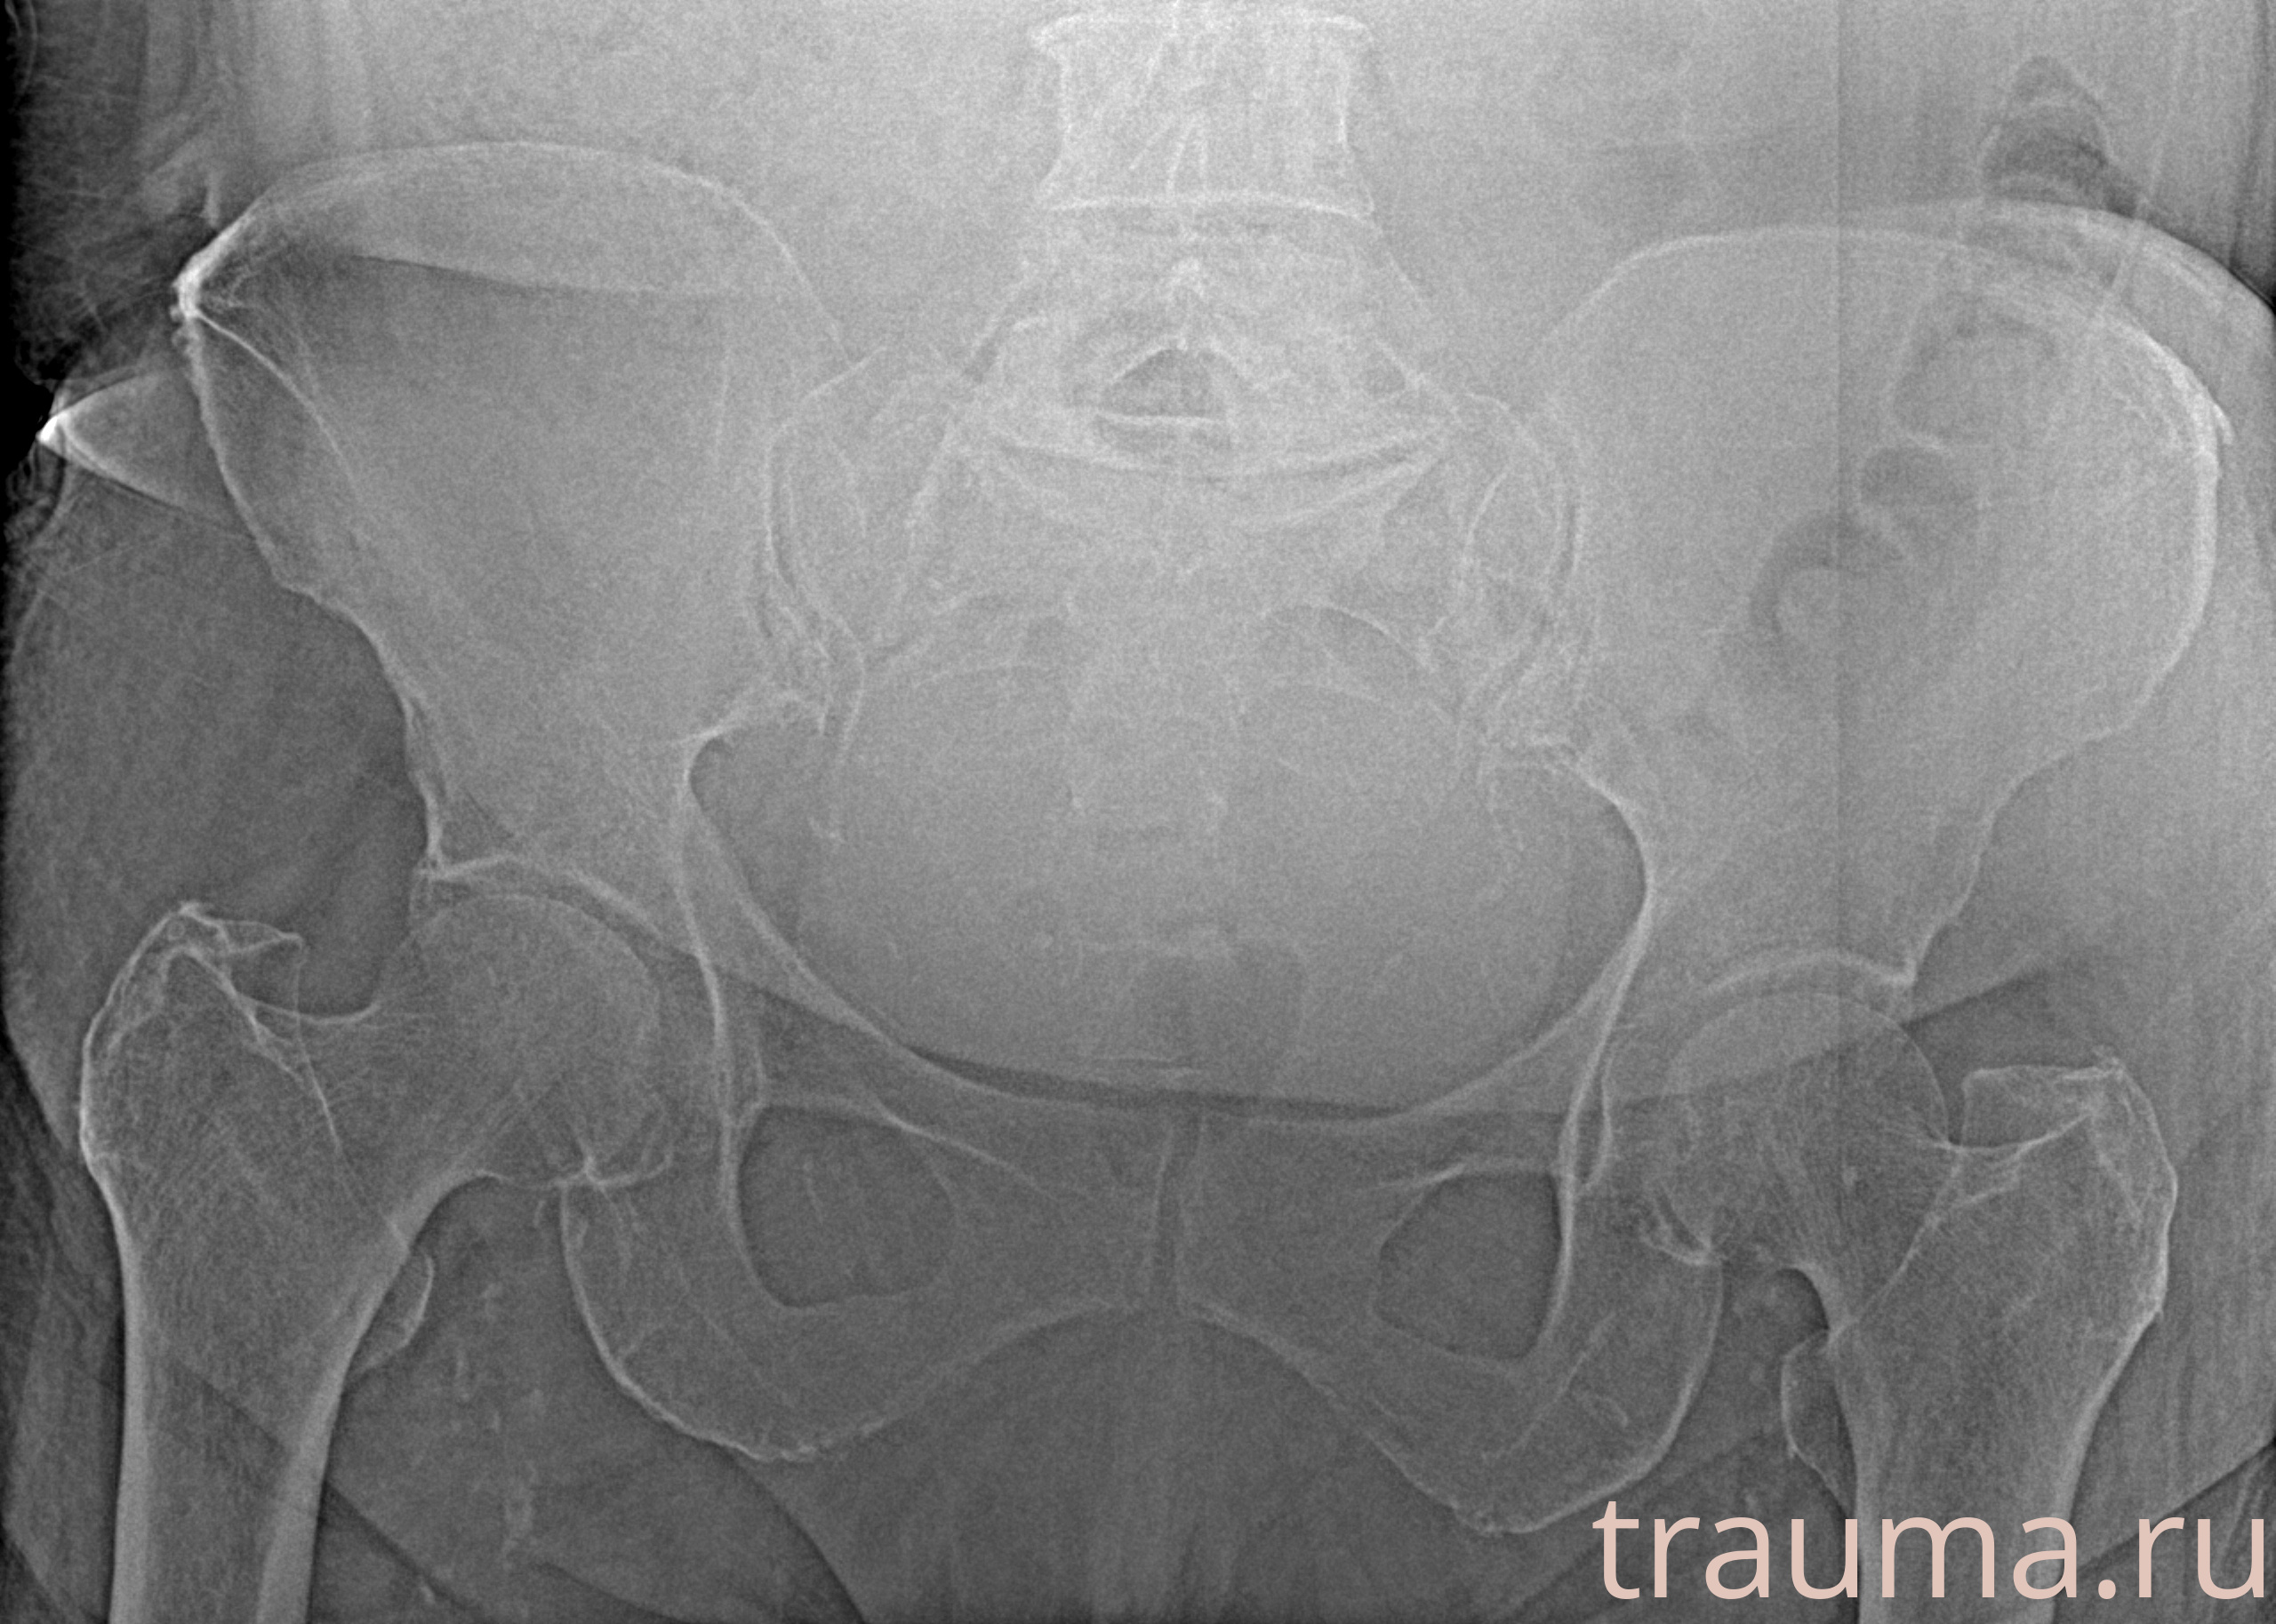

Рентгенограммы

Рентген на дому: по вашему адресу приезжает врач-рентгенолог, травматолог-ортопед с мобильным рентгеновским аппаратом, проводит диагностику травмы или заболевания, делает необходимые рентгенограммы, дает рекомендации по дальнейшему лечению. Получить качественные снимки в домашних условиях возможно благодаря уникальной методике, разработанной МосРентген Центром для института  Склифосовского